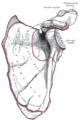

Acromion of left scapula01.png

عظم الكتف الأيسر. صورة أمامية. يظهر الأخرم باللون الأحمر.